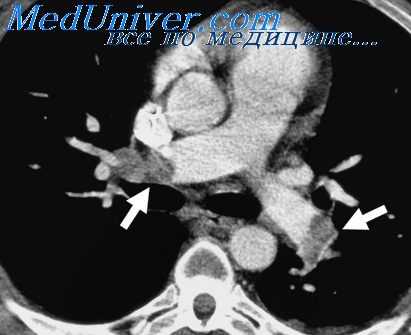

2. Выявление неоперабельных форм рака легкого вследствие прорастания магистральных сосудов в средостении. К числу ангиографических признаков неоперабельности больных раком легкого относятся сужение, дефект наполнения или полная обструкция верхней полой вены; сужение, деформация или ампутация легочной артерии в ее медиастинальном отрезке; одновременное сужение обеих долевых ветвей; дефект наполнения в предсердии; длительный стаз контрастного вещества в легочных венах (Slesser, Britt, Freer, 1954; Stiller, 1954; A. H. Новиков, А. X. Tpax-тенберг, С. Я. Марморштейн, 1964, и др.).

4. Диагностика пороков развития легочных сосудов (артериовенозная аневризма, аплазия правой или левой легочной артерии и др.).